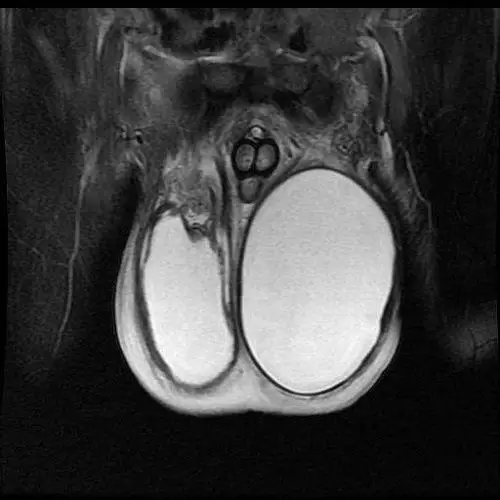

男性生殖系统超声诊断ppt课件